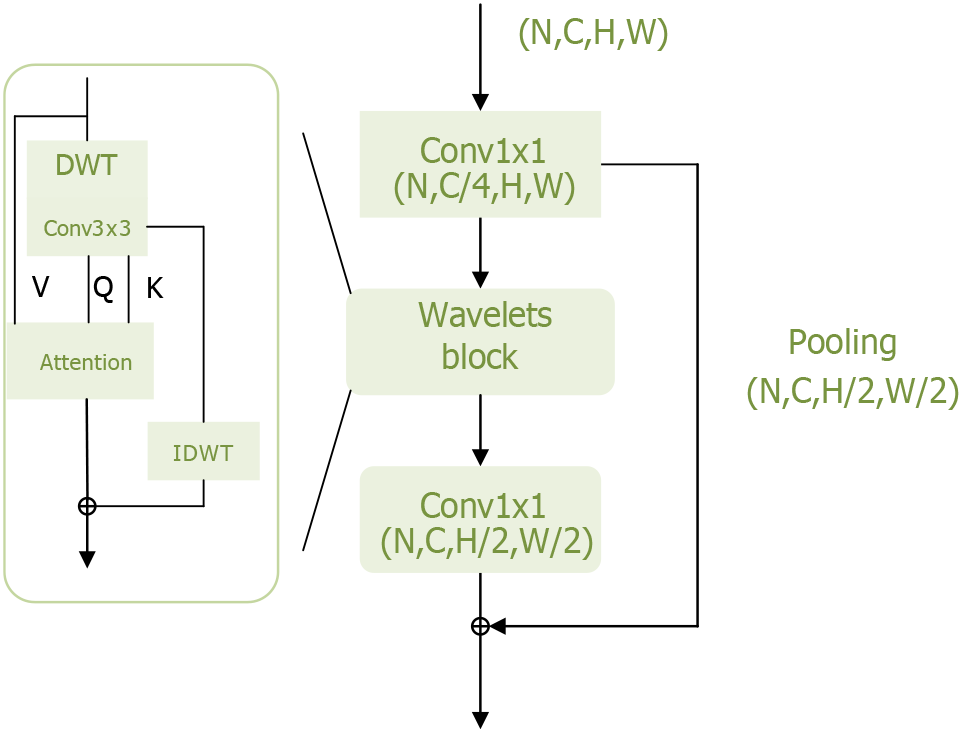

To further improve model performance, it is crucial to minimize information loss, particularly regarding high-frequency components such as texture details within the target. Yao et al[20] addressed this by modifying the transformer structure based on wavelet transforms, enabling the model to extract more frequency domain information and thereby enhance its performance. The wavelets module of the Wave-ViT model is shown in Figure 5.

The wavelets module performs reversible downsampling through wavelet transform, aiming to retain original image details for self-attention learning while reducing computational costs. Wavelet transform is a fundamental time-frequency analysis method that decomposes the input signal into different frequency sub-bands to address aliasing issues. Specifically, discrete wavelet transfor achieves reversible downsampling by transforming 2D data into four discrete wavelet sub-bands. Here, the low-frequency component reflects the coarse-grained structure of the primary object, while the high-frequency component retains fine-grained texture details[35]. In this way, different levels of image detail are preserved in lower-resolution sub-bands without information loss. Additionally, inverse discrete wavelet transform can be used to reconstruct the original image in the wavelet ViTs. This information-preserving transform enables the design of an efficient transformer block with lossless and reversible downsampling, facilitating self-attention learning on multi-scale feature maps.